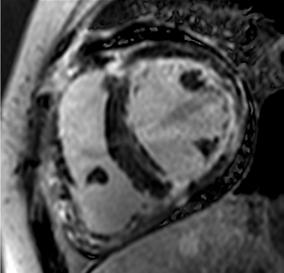

The cardiovascular magnetic resonance protocol used for assessment of hypertensive patients. The described protocol can be acquired within 45–50 min. Images are examples from patients with hypertensive heart disease.

Similar to echocardiography, LV geometry can be assessed using relative wall thickness (RWT) and CMR-specific normal values for LV myocardial mass (Figure 2). LA dimensions can be assessed with Simpson’s biplane or area-length methods from the standard views, or more precisely with a volumetric assessment using an atrial short-axis stack. LA enlargement is a reliable marker of diastolic dysfunction (chronically elevated LV filling pressures) in the absence of mitral valve disease [31]. The recently introduced left atrial coupling index (LACI) is a ratio of the indexed left atrial end-diastolic volume (LAVI) in relation to the left ventricular end-diastolic volume (LVEDVI) [32]. This ratio may offer prognostic information regarding cardiovascular events such as atrial fibrillation, heart failure, and coronary artery disease-related death.

Figure 2.

Tissue characterization with Late Gadolinium Enhancement (LGE) and Extracellular Volume (ECV) Map. Adapted with permission from [33].